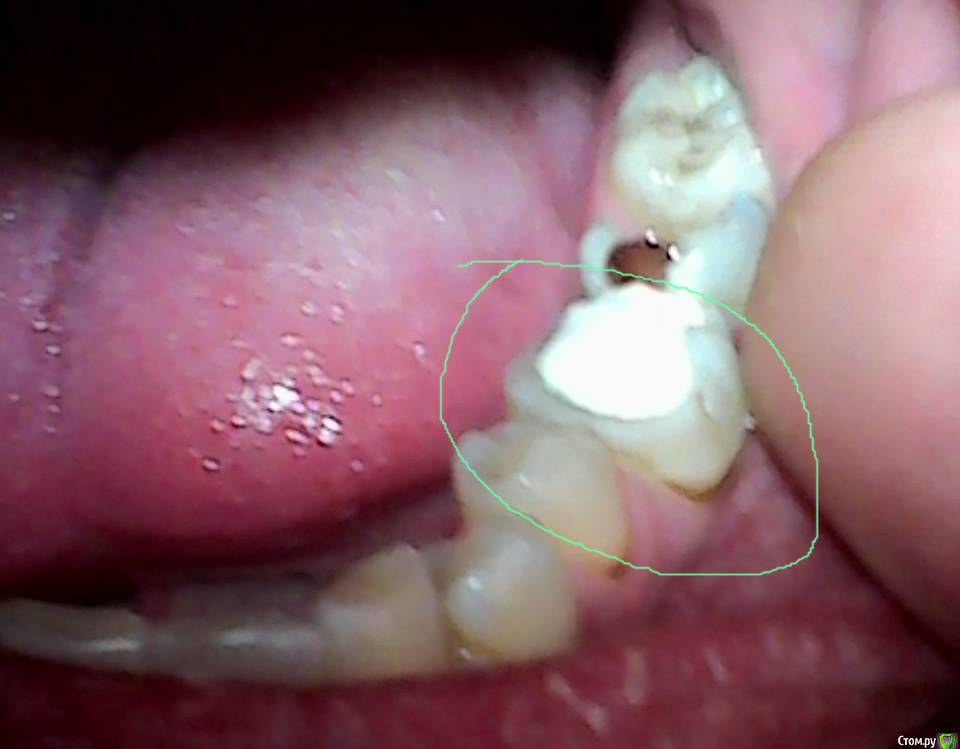

pils Опубликовано 15 августа, 2015 Поделиться Опубликовано 15 августа, 2015 Чтобы прокомментировать Вашу ситуацию компетентно, надо было бы видеть рентгены и качественную фотографию зуба. Я, например, глядя на то фото, что предоставили нам на суд Вы, вижу отсутствие язычной стенки, так что утверждение про большой и белый зуб как минимум преувеличено. Про внутренние проблемы я не совсем понял, что Вы имеете в виду, но как их может не быть, если нерв удален?И наконец, я думаю, что сам вопрос о "качественной пломбе" и "куче денег за спиливание" Вы ставите неверно. Ваш доктор, судя по фото, совершенно правильно говорит о том, что на пломбу для подобной полости гарантию дать не сможет, да и, будучи в здравом уме, даже делать этого не станет.Вкладка и коронка в данной ситуации, опять же, судя по фото, является адекватным методом лечения. Ваш зуб сильно разрушен и для качественного восстановления требуется трудоемкая, квалифицированная работа, за что, естественно, с Вас будут просить деньги.Также возникает вопрос о том, что Вы уже заранее готовы "качественную пломбу" менять через пару лет и готовы к тому, что "поплохеет". Понимаете ли Вы, что в случае вторичного кариеса при определенных обстоятельствах может потребоваться повторное лечение каналов и дополнительное сверление зуба (то самое спиливание)? Вы думаете, что это будет дешево? И все равно придете к тому, что придется делать пресловутые коронку и вкладку!Опять же возникает вопрос, зачем Вы идете к врачу, которому не доверяете и подозреваете его в сшибании денег? И наконец, если Вы просто строго лимитированы по своим средствам, то лучше сделайте один раз и нормально - в итоге выйдет дешевле! 3 Ссылка на комментарий